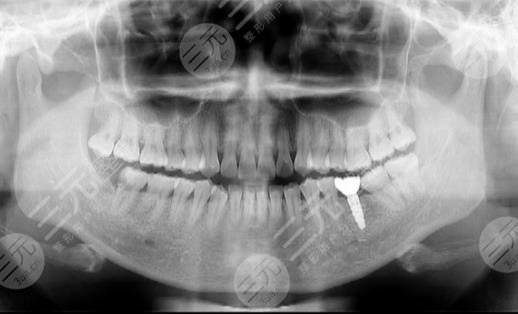

到醫(yī)院進(jìn)行面診的時(shí)候,醫(yī)生先讓我咬了牙齒的模型,然后又拍了牙片,選擇了牙齒的種植體,一星期之后,我來到了醫(yī)院進(jìn)行種植牙。整個(gè)種植牙的過程是很快的,而且因?yàn)榇蛄司植縨z也沒有任何的感覺。大家現(xiàn)在可以看到我的種植牙是十分成功的,而且看上去十分的潔白,跟周圍的牙齒形成了鮮明的對(duì)比。